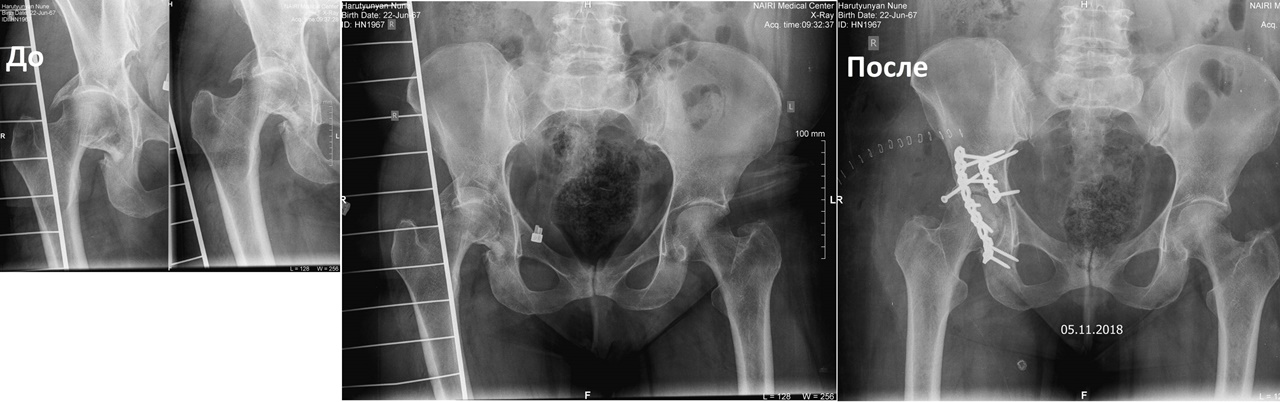

Dr. Hrachya G. Harutyunyan - Leading Orthopedic Surgeon of the Armenian-Finnish Clinic of Orthopedics COXA - NAIRI; specialized in hip and knee joint replacement, knee, elbow, ankle arthroscopy, bankart repair and acromioplasty, rotator cuff plasty, FAI reconstruction, Hallux valgus correction and more.